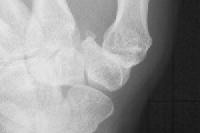

Same thumb after surgery, the reconstructed joint visible as an even space around the metacarpal base.